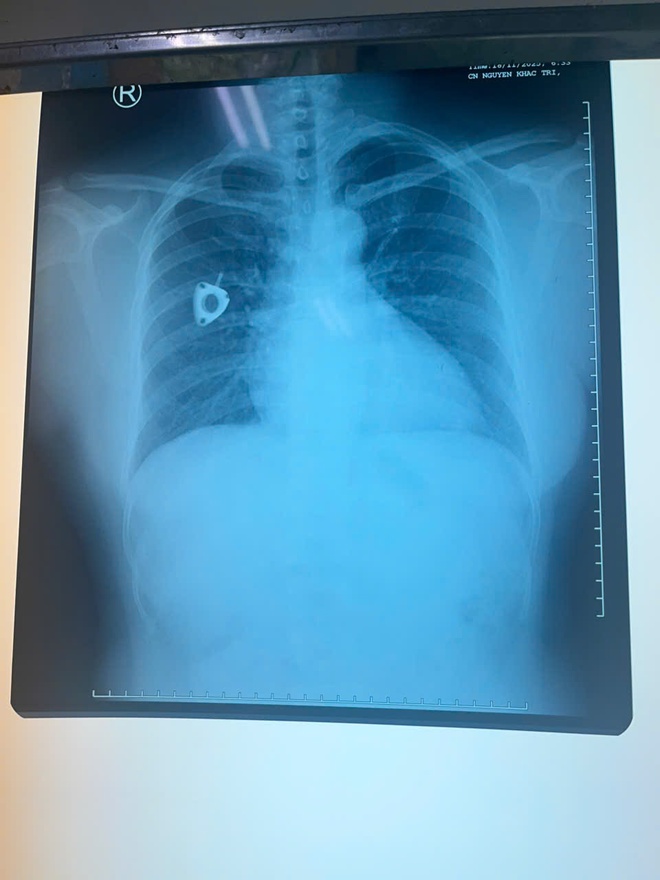

Hình ảnh CT-Scan sau khi rút dị vật

Ê-kíp đã lựa chọn phương pháp lấy dị vật qua đường tĩnh mạch đùi, tránh phẫu thuật mở ngực – mổ tim vốn tiềm ẩn nhiều rủi ro và thời gian hồi phục kéo dài. Dụng cụ snare chuyên dụng được đưa từ tĩnh mạch đùi lên tĩnh mạch chủ dưới, vào nhĩ phải, qua van ba lá đến thất phải và tiếp cận động mạch phổi. Tại vị trí phân nhánh động mạch phổi, một điểm rất khó tiếp cận, ê-kíp đã gắp chính xác đoạn catheter bị đứt và đưa ra ngoài an toàn.

Nhờ kỹ thuật ít xâm lấn, ca can thiệp diễn ra thuận lợi, bệnh nhân tỉnh táo ngay sau thủ thuật, hồi phục tốt và xuất viện sau theo dõi ngắn.